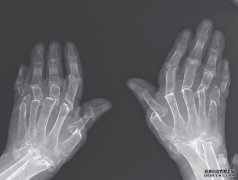

一种罕见的疾病导致女性手部和手指的骨骼萎缩。 据一份病例报告显示,一种罕见的情况导致一名女性的手指回缩,而她的手和手腕的骨头...